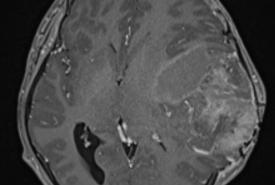

Temporal Ependymoma: A Case Study Emphasising Diagnostic Dilemmas and Therapeutic Challenges

Case Report 27 Jan, 2025